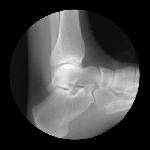

JOINTS IN MOTION

Cameron Drake of San Francisco has created a collection of magnificent images showing joints in motion. He was aided by orthopedic physician Dr. Noah Weiss and the finished product is completely amazing. If you’d like to know more about the project, please check out Drake’s blog.